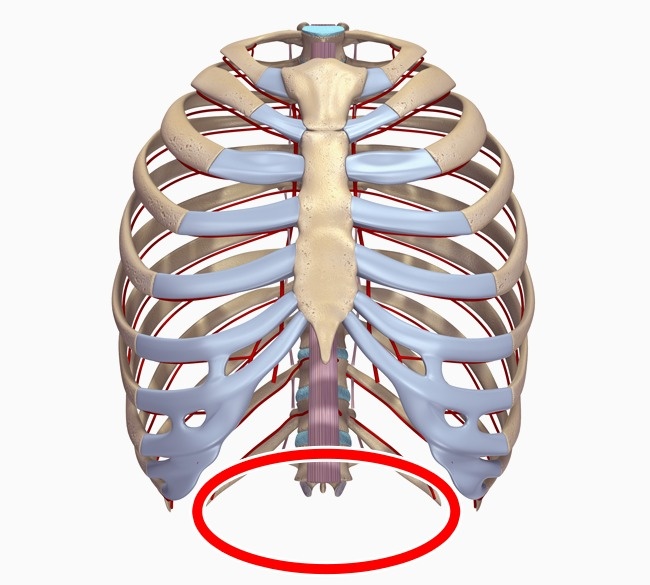

10. 第13對肋骨。

人類的近親—大猩猩和黑猩猩就有多一對肋骨,但人類通常只有12對,只有8%的成人會多一對肋骨。